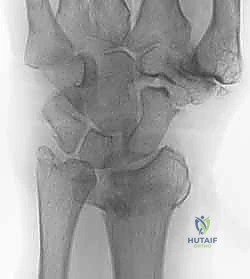

- الأشعة السينية (X-rays):

هي الخطوة الأولى لتقييم الكسر. يتم أخذ صور من زوايا متعددة (أمامية خلفية، جانبية، ومائلة) لتحديد موقع الكسر الأساسي ودرجة الانزياح والتقصير في عظم الكعبرة.

- التصوير المقطعي المحوسب (CT Scan) مع إعادة البناء ثلاثي الأبعاد:

هذا هو المعيار الذهبي الذي يعتمده الدكتور هطيف لجميع كسور المفصل المعقدة. تتيح الأشعة المقطعية رؤية كل شظية عظمية بوضوح تام، وتحديد حجمها، وموقعها، ودرجة تفتت السطح المفصلي بدقة ملليمترية. من خلال إعادة البناء ثلاثي الأبعاد (3D Reconstruction)، يمكن للدكتور هطيف "رؤية" الكسر من جميع الزوايا قبل فتح الجلد، مما يسمح له باختيار الغرسات (الصفائح والمسامير) الدقيقة لكل شظية وتحديد المداخل الجراحية المثلى.